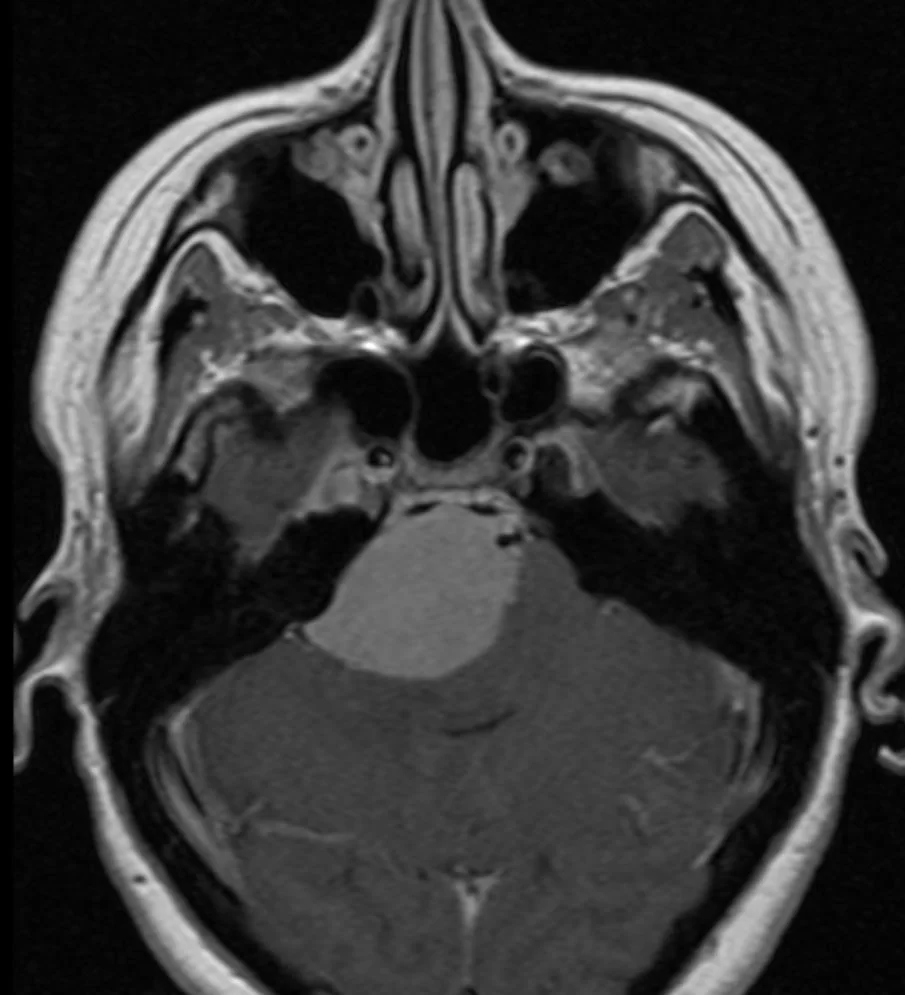

Γαγγλιογλοίωμα Ιπποκάμπου αριστερά

Ασθενής άνδρας, 38 ετών με πολλαπλά λιποθυμικά επεισόδια μετά από οσφρητική αύρα (επιληπτικές κρίσεις). Ο απεικονιστικός έλεγχος με μαγνητική τομογραφία